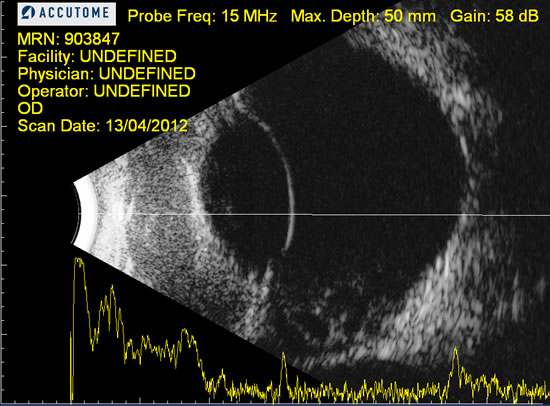

En medicina veterinaria, nuestros pacientes pocas veces presentan síntomas a no ser que la patología esté desencadenando estadíos fínales. Es en este momento cuando nos encontramos opacidades: edema corneal, endotelitis, turbiedad de humor acuoso por uveítis, cataratas, etc que impiden visualizar los componentes del ojo. La oftalmoscopia pasa a un segundo plano, recurriendo al ultrasonido.

En la actualidad se considera la modalidad de imagen como elección en el diagnóstico y control de las enfermedades oculares.